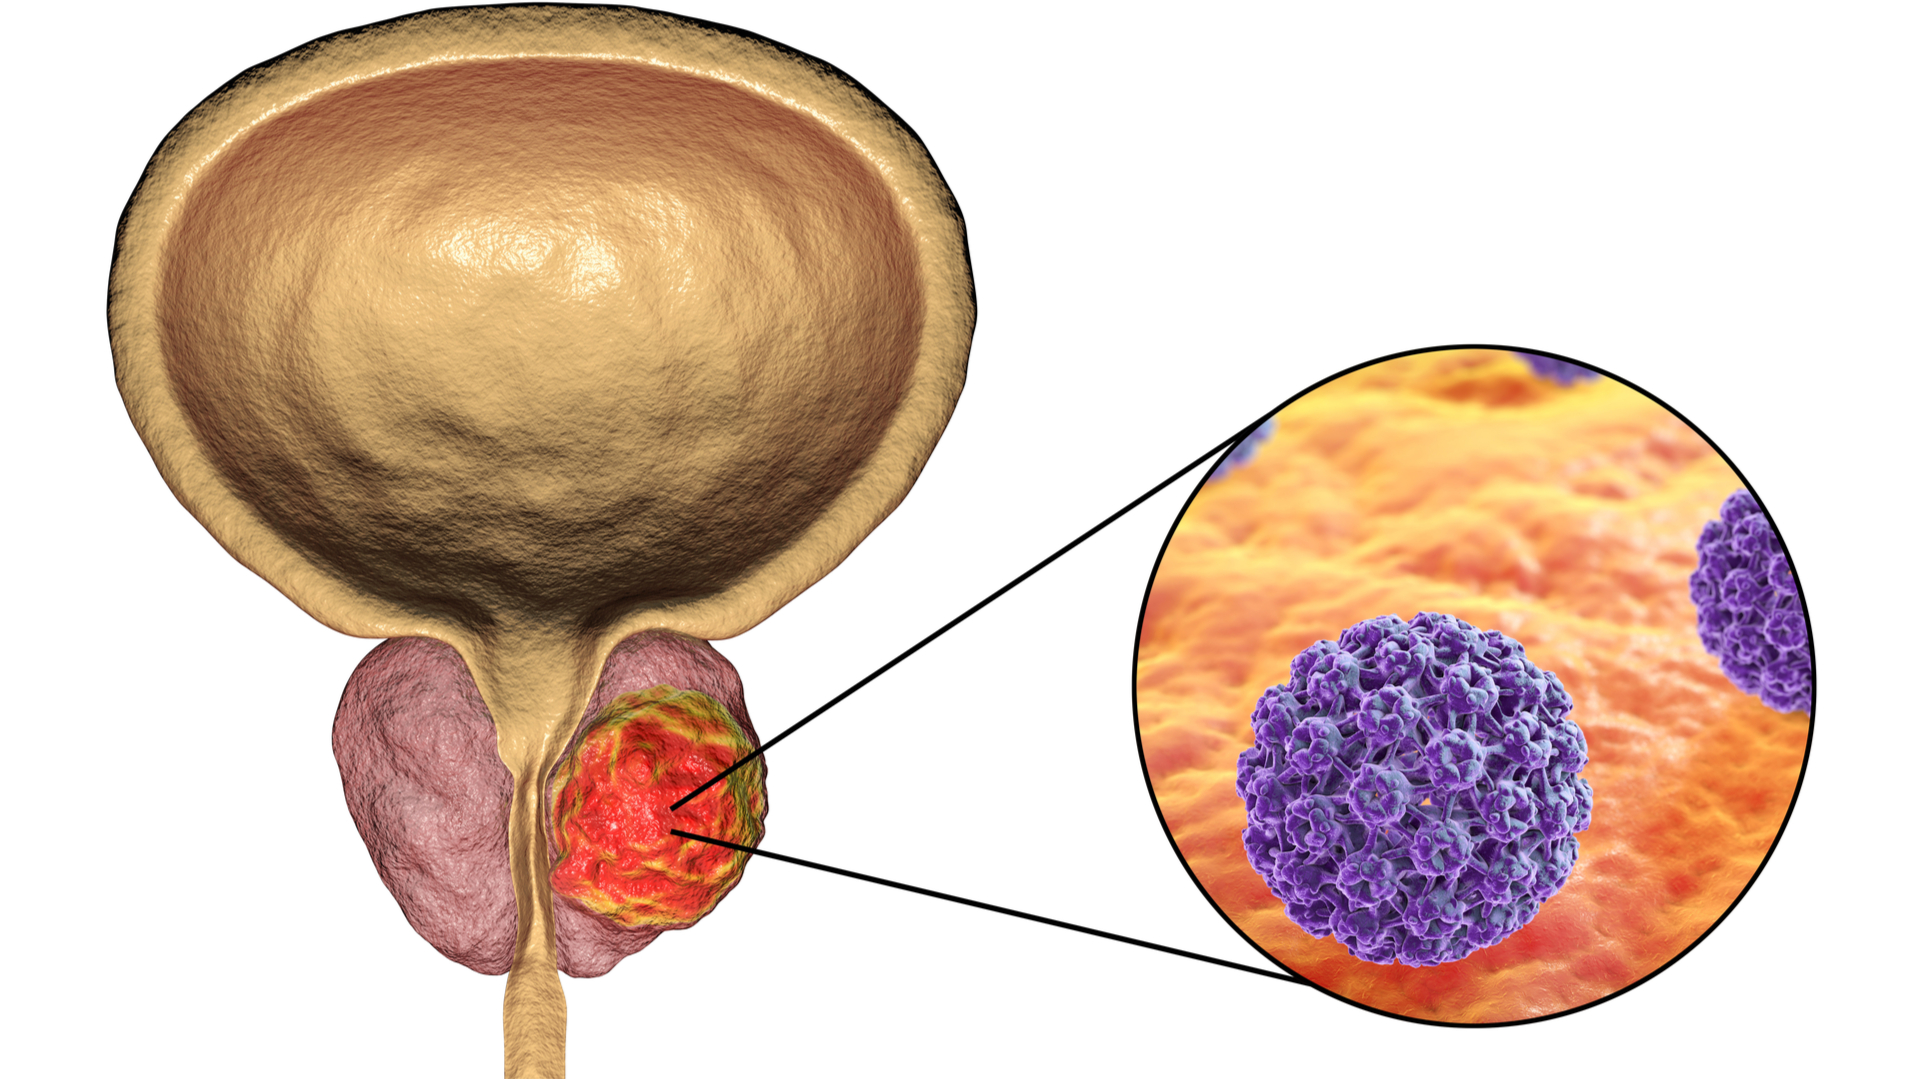

Простата, обычно ассоциируемая с мужским здоровьем после полового созревания, также присутствует у детей, хотя и в значительно меньших размерах. Этот орган, расположенный под мочевым пузырем и окружающий уретру, играет роль в выработке жидкости, которая составляет часть семенной жидкости. Несмотря на то, что проблемы с простатой у детей встречаются редко, понимание её развития и потенциальных патологий важно для ранней диагностики и лечения.